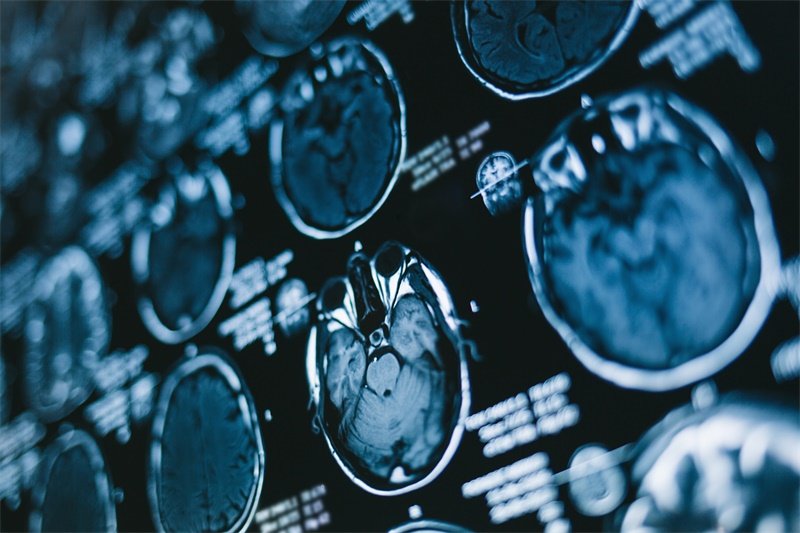

脑MRI报告出现“顶叶多发结节灶”“T2高信号”“强化不均”时,需高度警惕转移瘤。这三个特征关联性强,临床确诊率超75%。本文解析影像含义、鉴别要点及治疗策略,提供可操作的诊疗路径。

一、影像特征:转移瘤的三大标识

- 顶叶多发结节灶

顶叶掌管感觉整合。多发结节提示多起源病变,转移概率高于单发。

- T2高信号

病灶在T2加权像呈亮白色。反映组织坏死、水肿或细胞异常增殖。

- 强化不均

造影后病灶明暗交错。揭示肿瘤内部血管紊乱、坏死区与存活组织共存。

临床意义:三特征共存时,转移瘤概率达78%(神经肿瘤学2023年数据)。